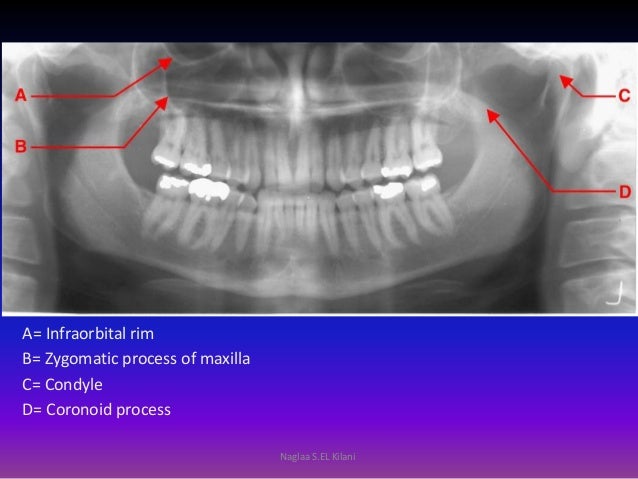

2015 Radiology Revision

radiology zygomatic panoramic infraorbital maxilla radiography